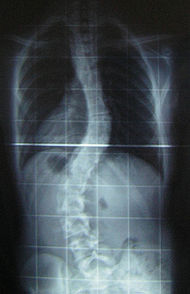

Ренгенологическое исследование сколиоза.

Является основным методом дополнительного исследования. Снимки делаются в переднезадней проекции лёжа и стоя. Целью исследования является установить этиологию, локализацию, степень искривления позвоночника и ротацию позвонков, признаки возможного прогрессирования.

Сколиотическое искривление позвоночника может иметь одну дугу, но чаще - две. В первом случае сколиоз называется простым «С» - образным, а во втором – сложным «S» - образным. Две дуги искривления могут быть обусловлены наличием первичной и компенсаторной дуги (компенсация искривления для удержания тела в вертикальном положении). Первичная дуга всегда более длинная и стабильная, а компенсаторная – короткая. Компенсаторная дуга более лабильна (непостоянна) и на ранних стадиях развития болезни может полностью исчезать в положении лежа.

Величина (угол) дуги искривления характеризует степень сколиоза.

(в градусах)

По В.Д. Чаклину По Дж. Коббу

I степень 180 175 меньше 15

II степень 175-155 20-40

III степень 155-100 40-60

IV степень меньше 100 больше 60